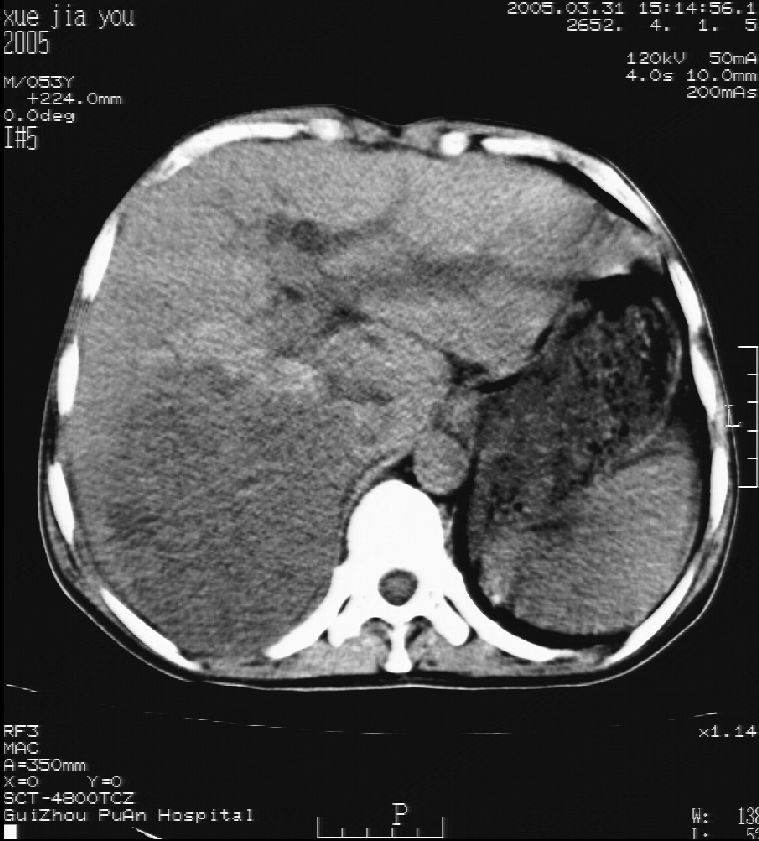

男 55岁  反复上腹痛1年,伴恶心呕吐。2005年做第一次检查后,到外院做b超检查提示肝囊肿,未做任何手术。2006年做过胆总管结石术。骨窗未见异常

这个病灶很有意思,怎么可能没有了呢?我考虑当时很可能是肝脏脓肿(b超示囊肿是有可能误诊的,因为影像表现都是低回声吗?),现在脓肿吸收了,肝脏萎缩,肝裂增宽了.别的肝叶代偿增大,不过现在左内叶的确有个占位,肝内多发结石,脾脏比以前大,不排除有肝硬化可能.建议增强扫描给于定性!!!!

肝硬化\\脾大,肝左叶肝癌可能性大,建议增强扫描.肝内胆管多发性结石.

1, 肝硬化,脾大;2,肝左叶肝癌可能性大,建议增强扫描.3,肝内胆管多发性结石.

考虑肝内胆管多发结石引起的肝内局部炎症,这样可以解释2005年肝右叶病灶的吸收和左叶新病灶.

肝硬化、脾大、肝内胆管多发结石。肝左叶低密度占位。建议增强扫描.排除肝癌